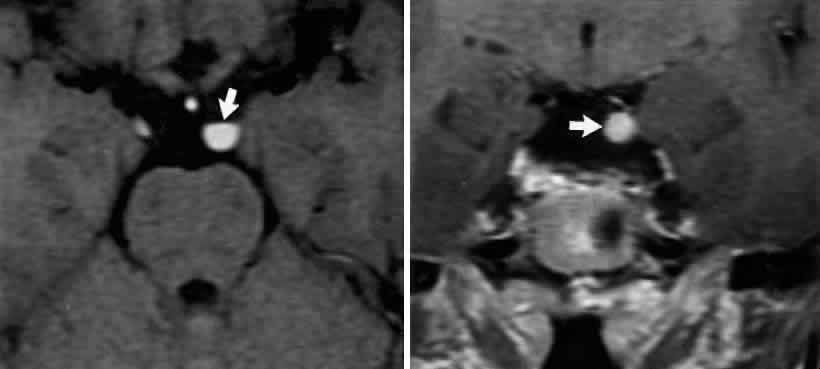

INTERPEDUNCULAR LESIONS

Basal lesions, including the rare rostral basilar artery aneurysm, may encroach on the oculomotor nerves as they exit in the interpeduncular space. Such slow-growing aneurysms, either saccular or fusiform, may present as partial oculomotor palsies with or without involvement of pyramidal tracts, and without subarachnoid hemorrhage.87 Aneurysms of the posterior communicating artery, on the other hand, are probably the most common lesions causing acute spontaneous oculomotor palsies (Fig. 12). According to Hyland and Barnett,88 the oculomotor palsy that occurs with posterior communicating aneurysm is not necessarily due to mass effect per se, but rather is attributed to hemorrhage that suddenly enlarges the aneurysmal sac to which the oculomotor nerve is adherent, or to hemorrhage into the substance of the nerve itself. Most patients present, therefore, with an intensely painful, complete unilateral oculomotor palsy in association with other signs and symptoms of subarachnoid hemorrhage. Few patients with symptomatic posterior communicating aneurysms are found in office waiting rooms: they are usually obtunded or comatose in emergency rooms.

Fig. 12. Sudden total right ophthalmoplegia accompanied by orbital pain, due to posterior communicating artery aneurysm. A. Complete right ptosis. B. Right eye in abducted position, with dilated pupil, fixed to light. C. Failure of adduction on left gaze. D. Right eye intorts (arrow) on downward gaze, indicating retained function of fourth nerve. E. Contrast-enhanced T-1 weighted MRI axial section shows aneurysm (arrows). Confirmed by angiography.